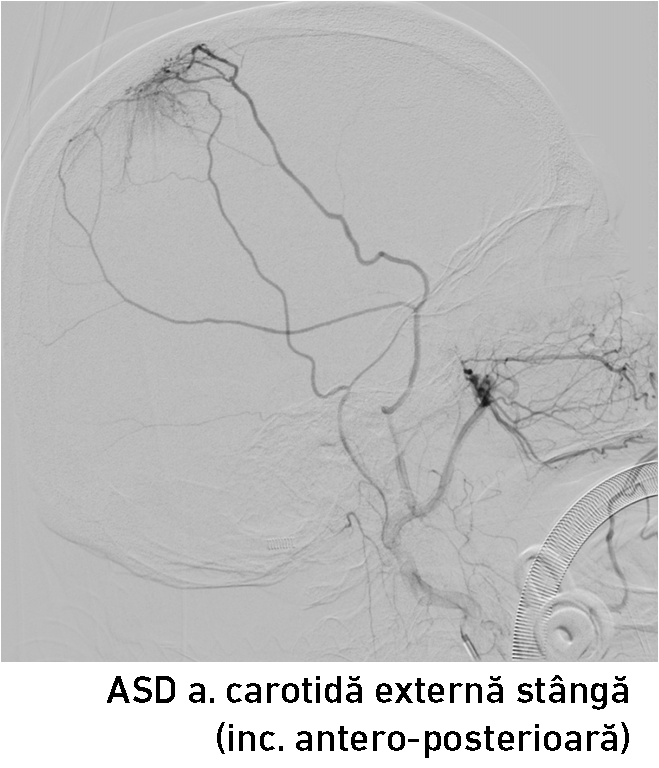

A fost decisă realizarea angiografiei cu substracție digitală a vaselor capului și gâtului preoperator, pentru aprecierea vascularizării tumorii și posibilităților tratamentului endovascular.

Angiografia clasică diagnostică a confirmat existența unui blush tumoral (fig. 3-4) – leziunea fiind alimentată de artera meningee medie (AMM) stângă și artera temporală superficială stânga (ramuri ale arterei carotide externe stângi). Echipa medicală a decis realizarea unei embolizări preoperatorii pentru a reduce hemoragia intraoperatorie și diminuarea riscului de recurență tumorală (care este dublu la meningioamele parasagitale !). Hemoragia intraoperatorie reprezintă un factor de risc major și poate împiedica chirurgul în realizarea unei exereze radicale a proceselor tumorale voluminoase.